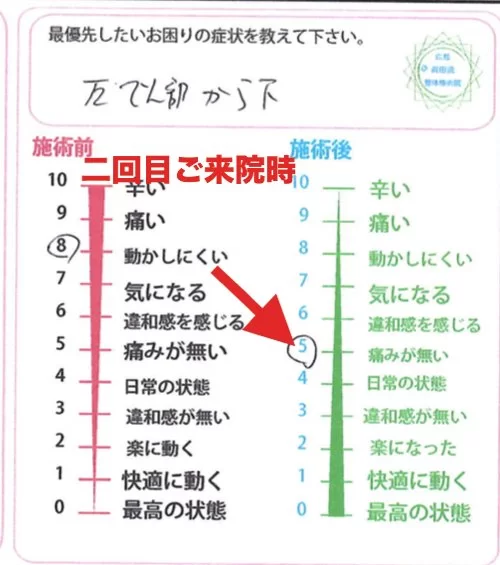

そして2ヶ月後・・・

本来なら1週間後くらいに来て欲しかったのですが^^;;

痛みも無く、調子が良かったのでついつい期間が伸びてしまったそうです。。

そして2回目の施術にお越し頂きましたが

初回ご来院の際に辛かった腰や脚の痛みは

前回の施術直後から無くなり

今日も痛みは無しで良好!

若干 筋肉が張ったような感じで

動かいにくいとのことでした。

動いた際に違和感を感じる部分はここと

ふくらはぎ。

そして足裏。

2回目施術前後のアンケート

施術前 8: 動かしにくい → 施術後 5:痛みが無い

山口県からなので、頻繁には来れないとは思いますが

せめて2週間に1回を2回続けて

そして1ヶ月後にもう1回施術に来て頂ければ

深部まで調整が出来て再発もしずらくなると思います。